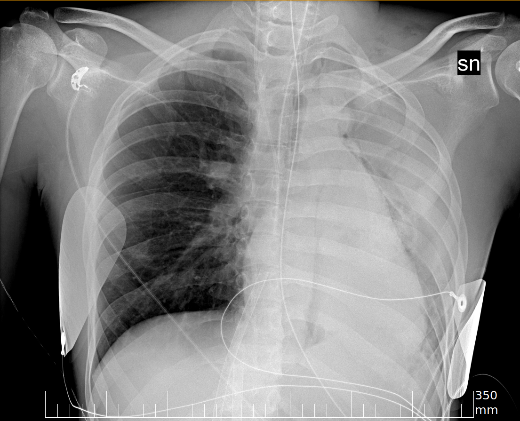

Early screening of patients is a critical issue in order to assess immediate and fast responses against the spread of COVID-19. The use of nasopharyngeal swabs has been considered the most viable approach; however, the result is not immediate or, in the case of fast exams, sufficiently accurate. Using Chest X-Ray (CXR) imaging for early screening potentially provides faster and more accurate response; however, diagnosing COVID from CXRs is hard and we should rely on deep learning support, whose decision process is, on the other hand, "black-boxed" and, for such reason, untrustworthy. We propose an explainable two-step diagnostic approach, where we first detect known pathologies (anomalies) in the lungs, on top of which we diagnose the illness. Our approach achieves promising performance in COVID detection, compatible with expert human radiologists. All of our experiments have been carried out bearing in mind that, especially for clinical applications, explainability plays a major role for building trust in machine learning algorithms.